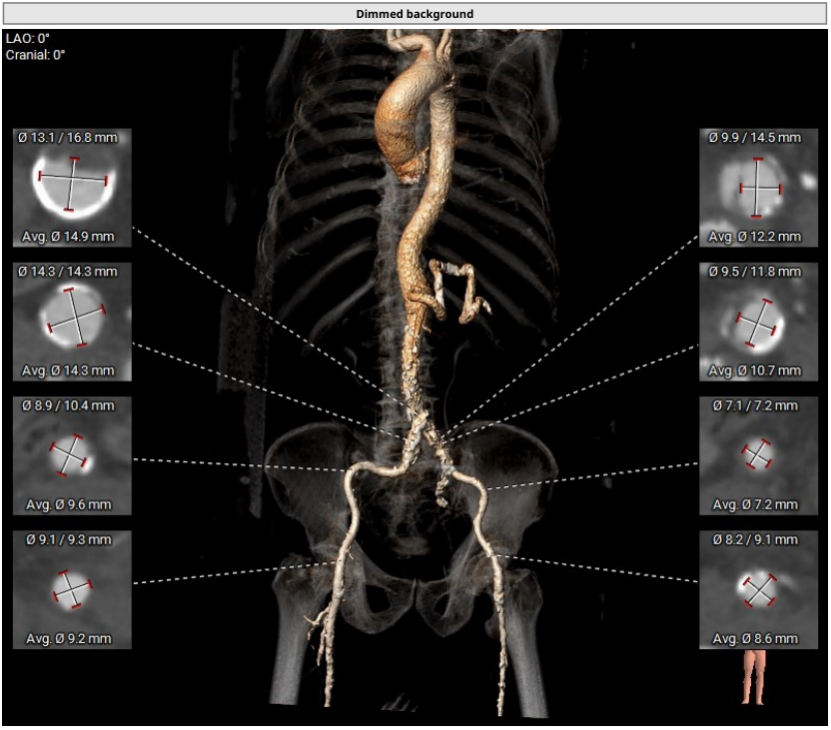

腹主动脉存在溃疡并附壁血栓,全主动脉可见散在钙化附着,血管内壁存在纤维增厚。 面对患者生存的渴望,在郑宝石教授的组织和指导下,心内科陈宇明主任医师团队协同心外科、超声医学科、麻醉科、导管手术室等,共同为冯大伯施行了TAVI。手术过程十分顺利,术后在医护团队的悉心照料下,冯大伯平稳度过了“感染关”“功能康复关”。